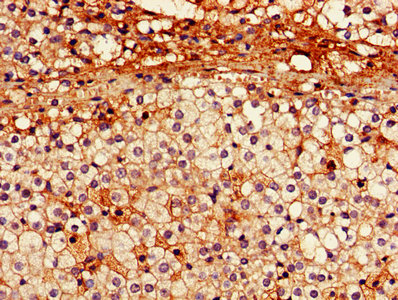

IHC image of CSB-PA017451LA01HU diluted at 1:600 and staining in paraffin-embedded human adrenal gland tissue performed on a Leica BondTM system. After dewaxing and hydration, antigen retrieval was mediated by high pressure in a citrate buffer (pH 6.0). Section was blocked with 10% normal goat serum 30min at RT. Then primary antibody (1% BSA) was incubated at 4°C overnight. The primary is detected by a biotinylated secondary antibody and visualized using an HRP conjugated SP system.